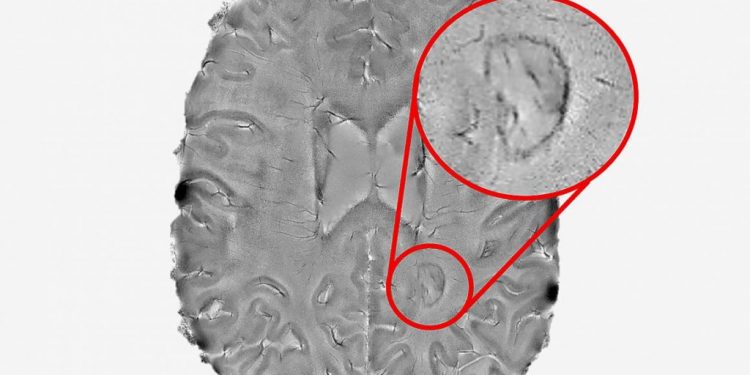

Эти поражения описанные как «темные края на краях», трудно увидеть. Поэтому исследователи использовали сверхсильный МРТ сканер, чтобы найти их. (Вы можете увидеть как это выглядит на картинке ниже).

Из 192 человек с РС в этом исследовании у 56 процентов было по крайней мере одно очаговое поражение, а у 44 процентов — только без оправы. Поражения присутствовали в мозге тех кто получал терапию, модифицирующую болезнь (ПИТРС), и у тех кто не проходил лечение ПИТРС.

Исследователи также рассмотрели МРТ-снимки, сделанные более 10 лет или дольше для небольшого подмножества основной группы. Они обнаружили, что их повреждения без оправы, как правило сокращались в течение десятилетия, но их повреждения с ободами либо росли либо оставались такими же.